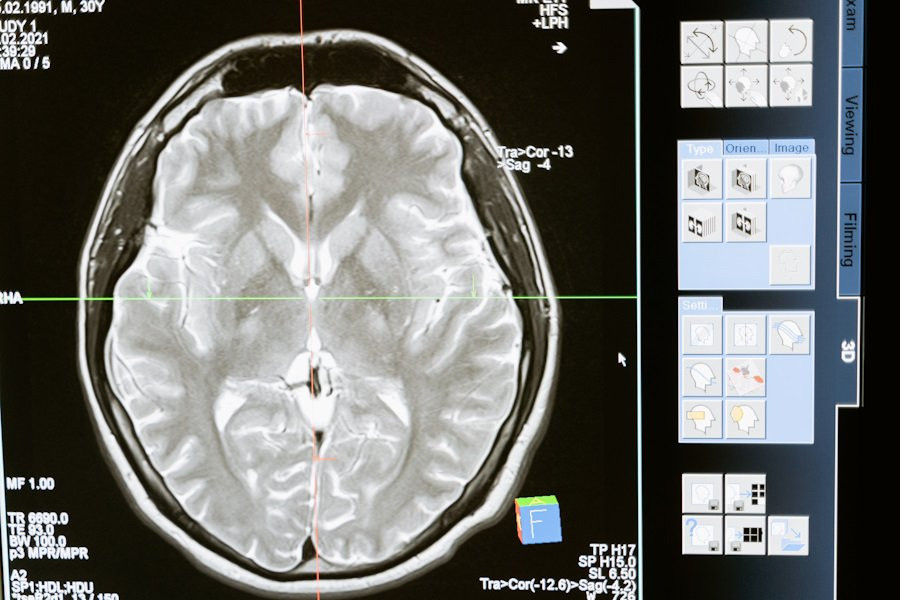

Нейробиологи РФ работают над созданием нейроинтерфейса, помогающем улучшить реакции у пожилых людей. Их исследования основаны на использовании транскраниальной магнитной стимуляции, или ТМС, сообщает ТАСС.

ТМС - это метод, при котором магнитные поля воздействуют на активные участки мозга. Этот метод может быть полезен в реабилитации после травм двигательного аппарата. Нейробиологи утверждают, что ТМС способствует активизации мозговой деятельности.